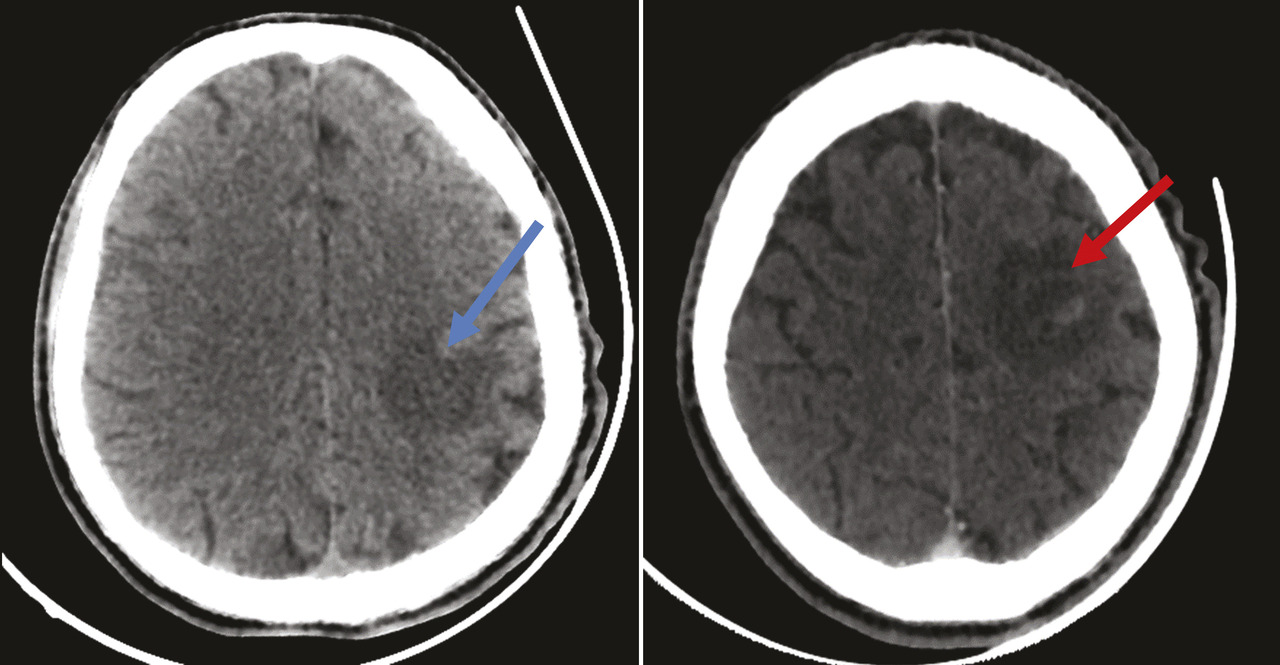

Un homme âgé de 51 ans, sans antécédents particuliers, a depuis deux semaines une hémiplégie droite et une dysarthrie évoluant dans un contexte d’apyrexie et d’altération de l’état général. À l’examen clinique, le patient, conscient, est stable sur le plan hémodynamique et respiratoire ; l’examen neurologique objective un déficit moteur de l’hémicorps droit. Les constantes sont les suivantes : température à 37,3 °C, pression artérielle de 125/75 mmHg, indice de masse corporelle (IMC) de 18,6 kg/m2. Le bilan biologique initial (hémogramme et protéine C-réactive) est normal. Le patient bénéficie en urgence d’une tomodensitométrie (TDM) cérébrale sans et avec injection du produit de contraste montrant des plages hypodenses éparses non systématisées avec prise de contraste annulaire après injection du produit de contraste (fig. 1 ). Par la suite, une imagerie par résonance magnétique (IRM) cérébrale caractérise ces multiples lésions parenchymateuses cérébrales sus- et sous-tentorielles en hypersignal T1, hypersignal T2 hétérogène, en hypersignal et Flair, avec une restriction sur la diffusion, se rehaussant en cible excentrée « target sign », avec œdème périlésionnel (fig. 2 ). Face à cet aspect radiologique, le diagnostic de toxoplasmose cérébrale est évoqué. Puis une sérologie toxoplasmique et au virus de l’immunodéficience humaine (VIH) se révèle positive, avec un taux de CD4 de 89 cellules/mm3. Le patient est traité par un antiparasitaire (pyriméthamine avec acide folinique) associé à une trithérapie antirétrovirale. Malgré une prise en charge rapide, l’évolution est marquée par une aggravation du tableau clinique, avec installation de troubles de la conscience ayant conduit au décès.